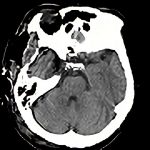

蝶形骨稜髄膜腫

断層撮影

手術前1

手術前2

手術後

No.’12_168 手術前1

No.’12_168 手術後